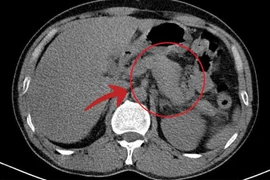

Trung tâm Y tế Cẩm Khê (Phú Thọ) vừa cứu sống bệnh nhân N.V.T. (46 tuổi) bị viêm tụy cấp nặng do mỡ máu Triglycerid tăng cao (gấp gần 80 lần bình thường).

Viêm tụy cấp do tăng triglycerid thường có biểu hiện lâm sàng nặng hơn so với các nguyên nhân khác, có nguy cơ cao hơn về suy đa tạng và các biến chứng khác.

Viêm tụy cấp do tăng mỡ máu thường nặng hơn và đe dọa tính mạng bệnh nhân hơn so với các nguyên nhân khác. Lọc máu liên tục là phương pháp mới hạn chế được nhược điểm của phương pháp thay huyết tương.